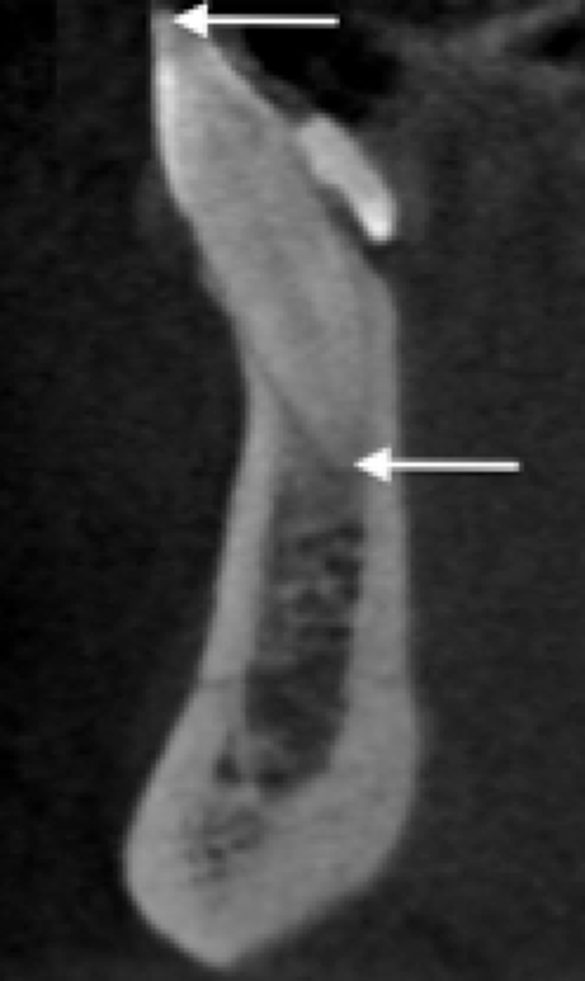

Dacă sinusul se extinde între rădăcini într-o formă triunghiulară, radiotransparența rezultată va fi adesea insuficientă pentru detectarea pe radiografiile periapicale, similar cariilor incipiente de la nivelul suprafețelor vestibulare/orale ale dinților. Prin urmare, se va înregistra o supraestimare la măsurarea înălțimii crestei alveolare.

De asemenea, înălțimea crestei alveolare poate părea mai lungă pe o radiografie PA decât într-o imagine pe secțiune transversală (fig. 9), deoarece suprapunerea va arăta că înălțimea ar fi la fel de mare ca cel mai înalt punct al crestei (diagrama nr. 1 din fig. 9). Cu toate acestea, în realitate, zona de interes pentru plasarea implantului (diagrama nr. 4 din fig. 9) poate avea o înălțime crestală inadecvată pentru plasarea chirurgicală convențională.